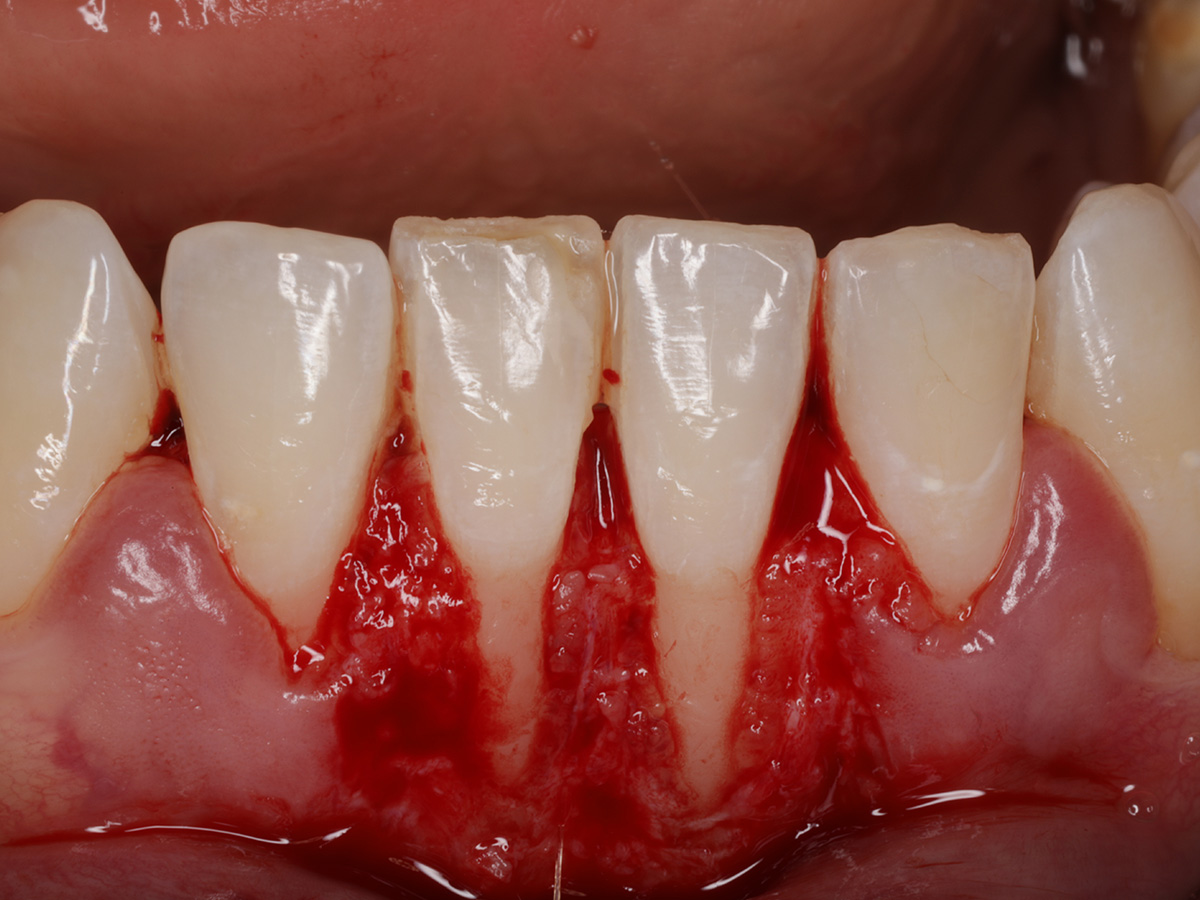

Abbildung 2

Präparation des Empfängerbetts für die Aufnahme eines freien Schleimhauttransplantates.